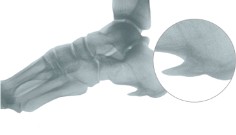

Sperone calcaneare talalgia

- Sovraccarico dell’arco longitudinale - irritazione periostale

- Dolore localizzato all’inizio della aponeurosi plantare